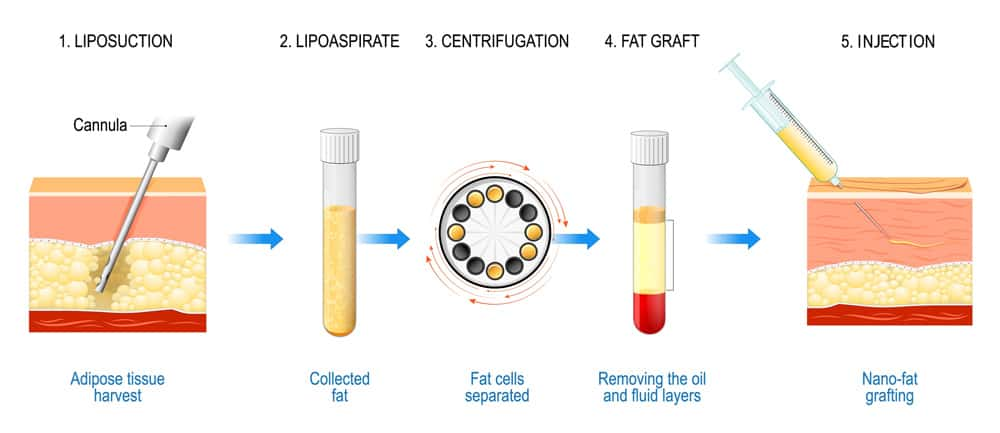

Fat Grafting

Fat grafting restores volume loss in the face, including both upper and lower eyelids, tear troughs, cheeks, and temples.Overview

Fat is harvested from areas like the abdomen or thighs.The fat is processed and purified.

Small injections are made into the target areas to restore volume and smooth contours.

Pros:

Natural filler using your own tissueImproves hollows, wrinkles, and facial symmetry

Minimal risk of allergic reaction

Cons:

Some fat may be resorbed over time, requiring touch-upsSwelling and bruising for 1–2 weeks

Requires experience to avoid lumps or irregularities

FAT GRAFTING BEFORE & AFTER

Price: €1,000–€4,000